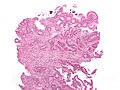

Hematoxylin and eosin stain of benign prostate. (WC) | |

| Interpretation | blue (hematoxylin) = nucleus, pink (eosin) = cytoplasm |

- Blue (hematoxylin) = nucleus.

- Pink (eosin) = cytoplasm.